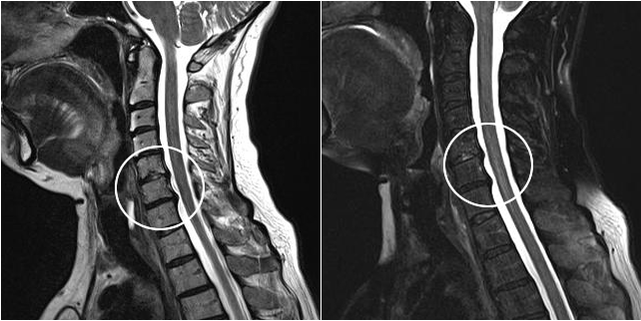

Diagnose einer Osteochondrose.

Eine Röntgenuntersuchung wird Aufschluss geben. Besonders in den späteren Stadien der Krankheit.

Zu den modernen Diagnosemethoden gehören MRT und CT, die eine genauere Untersuchung der Zerstörungsprozesse von Knorpel- und Knochengewebe ermöglichen. Darüber hinaus ist es mit dieser Technik bequem, Hernien und andere Weichteildefekte in der Nähe des Krankheitsherdes zu diagnostizieren.